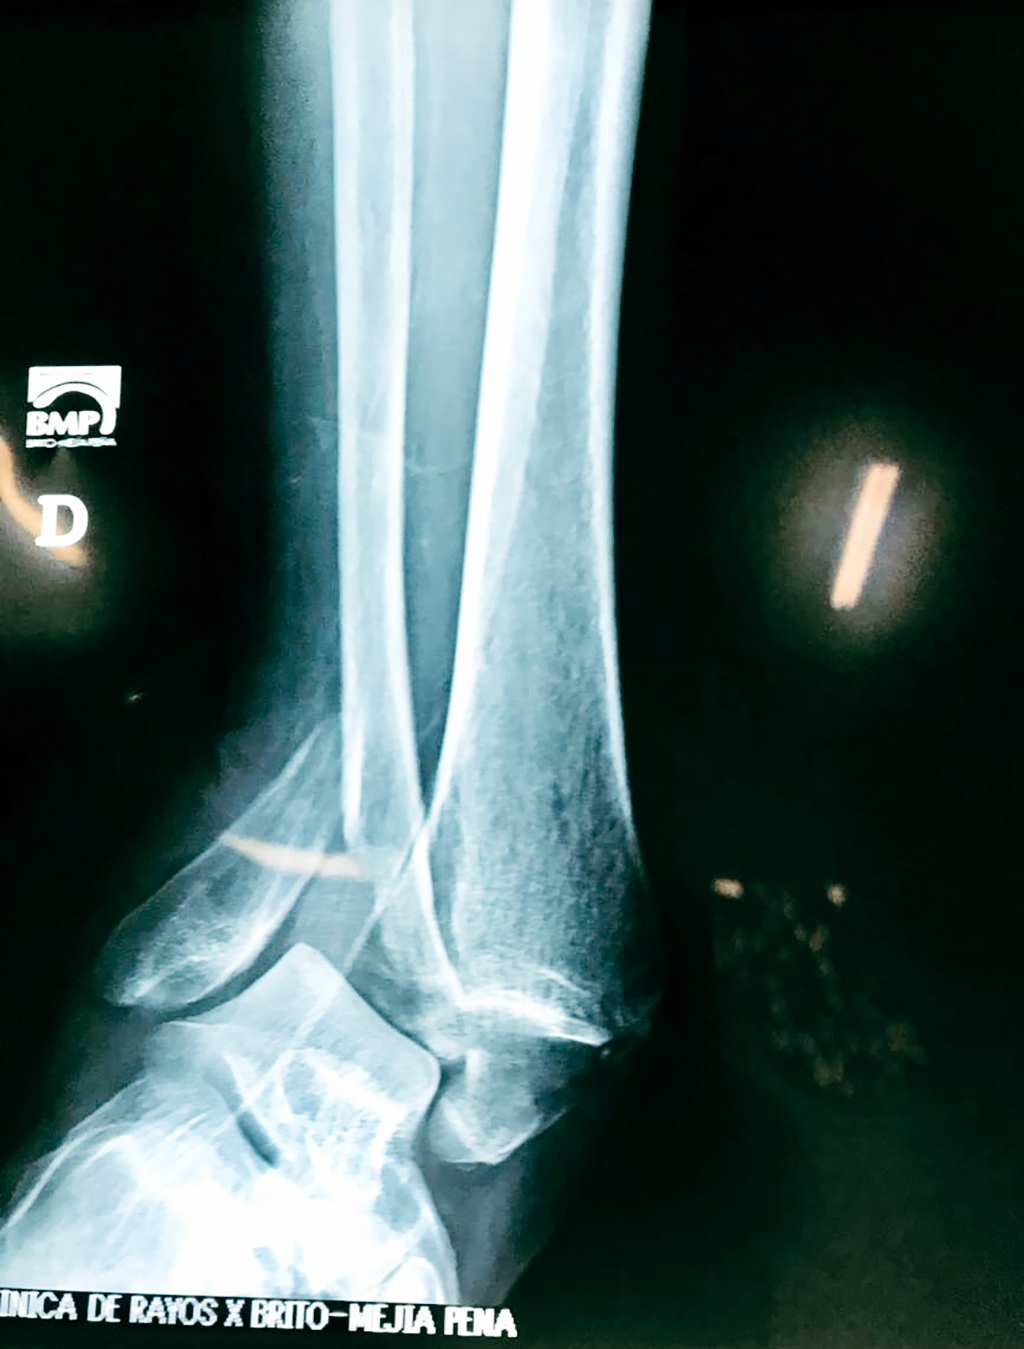

Una fractura de tobillo es la rotura de uno o más de los huesos del tobillo. Estas fracturas pueden ser:

- Los extremos de los huesos están desalineados entre sí (desplazados).

- La fractura se extiende hasta la articulación del tobillo (fractura intra-articular).

- Los tendones o ligamentos (tejidos que sujetan los músculos y los huesos entre sí) están rotos.

Cuando se necesita cirugía, es probable que esta implique el uso de clavijas de metal, tornillos o placas para sostener los huesos en su lugar mientras la fractura se consolida. Los elementos de soporte pueden ser temporales o permanentes.